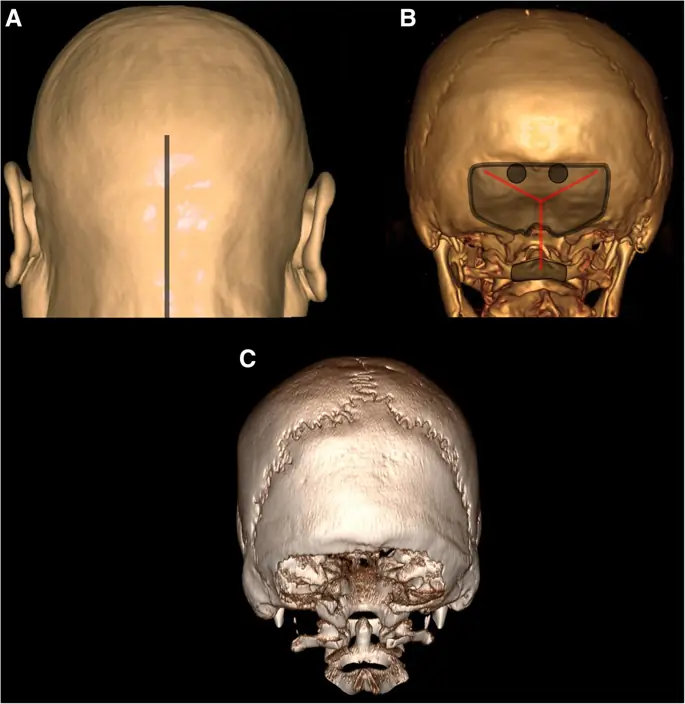

Рисунок 3

Оперативная техника супратенториального округа Колумбия. Исполнение художника человеческой головы (а) с типичной линией разреза для DC (серая линия). Трехмерная реконструкция человеческого черепа (б) с демонстрацией заусенцев (серые круги), краниэктомии (серая область) и дополнительной остеокластической декомпрессии дна средней черепной ямки (заштрихованная область), а также типичного разреза дурала (красные линии). Трехмерная реконструкция человеческого черепа (с) с типичным дефектом черепа при гемикраниэктомии. Интраоперационная фотография мозга человека после ДК (г)

Оперативная техника инфратенториального ДК. Исполнение художника человеческой головы (а) с типичной линией разреза для субокципитального DC (серая линия). Трехмерная реконструкция человеческого черепа (б) с демонстрацией заусенцев (серые круги), краниэктомии и удалением задней дуги атласа (серые области), а также типичного разреза дурала (красные линии). 3D реконструкция человеческого черепа (с) с типичным субокципитальным дефектом черепа DC